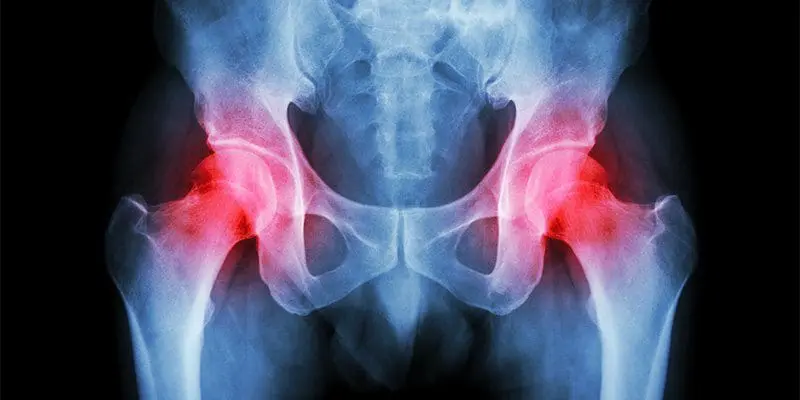

Hip pain is a well-known health issue which can be caused by a wide array of problems, however, the site of the patient’s hip pain can provide valuable information regarding the underlying cause of this common health issue. Pain on the inside of the hip or groin can be due to problems within the hip joint itself while pain on the outside of the hip, upper thigh and outer buttocks may be due to problems with the ligaments, tendons and muscles, among other soft tissues, surrounding the hip joint. Furthermore, hip pain can be due to other injuries and conditions, including back pain.

Hip pain is a common and disabling condition that affects patients of all ages. The differential diagnosis of hip pain is broad, presenting a diagnostic challenge. Patients often express that their hip pain is localized to one of three anatomic regions: the anterior hip and groin, the posterior hip and buttock, or the lateral hip. Anterior hip and groin pain is commonly associated with intra-articular pathology, such as osteoarthritis and hip labral tears. Posterior hip pain is associated with piriformis syndrome, sacroiliac joint dysfunction, lumbar radiculopathy, and less commonly ischiofemoral impingement and vascular claudication. Lateral hip pain occurs with greater trochanteric pain syndrome. Clinical examination tests, although helpful, are not highly sensitive or specific for most diagnoses; however, a rational approach to the hip examination can be used. Radiography should be performed if acute fracture, dislocations, or stress fractures are suspected. Initial plain radiography of the hip should include an anteroposterior view of the pelvis and frog-leg lateral view of the symptomatic hip. Magnetic resonance imaging should be performed if the history and plain radiograph results are not diagnostic. Magnetic resonance imaging is valuable for the detection of occult traumatic fractures, stress fractures, and osteonecrosis of the femoral head. Magnetic resonance arthrography is the diagnostic test of choice for labral tears.

The hip joint is one of the larger joints found in the human body and it serves in locomotion as the thigh moves forward and backward. The hip joint also rotates when sitting and with changes of direction while walking. A variety of complex structures surround the hip joint. When an injury or condition affects these, it can ultimately lead to hip pain.